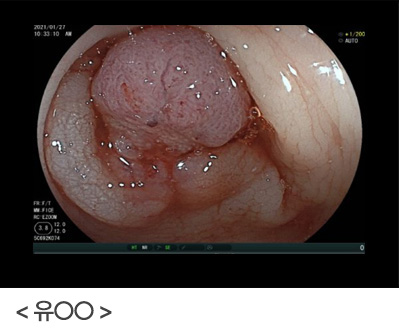

위암도 초기에는 대부분 아무런 증상이 없는 경우가 많으며, 정기적인 위내시경 도중 우연히 발견되는 경우가 많고, 진행된 위암의 경우, 오심, 구토, 소화불량 등의 증상이 나타날 수 있습니다. 정기적인 위내시경 검사를 통해 위를 직접 관찰하고 필요시 조직 검사를 통해 위암이 의심되는 부위를 확인함으로써 위암을 조기에 발견할 수 있습니다.